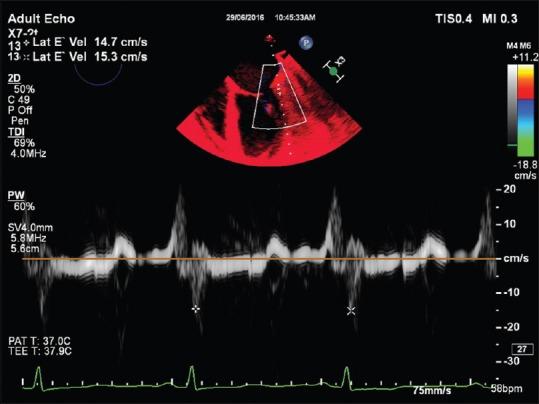

Left ventricular global systolic function assessment by echocardiography.

The left ventricle, with its thickened myocardial walls, unlike the right ventricle has no measurable geometric shape. It has a conical apex and its function quantification, needs intensive, 2D, 3D and M mode transesophageal echocardiography, which is described in this review.